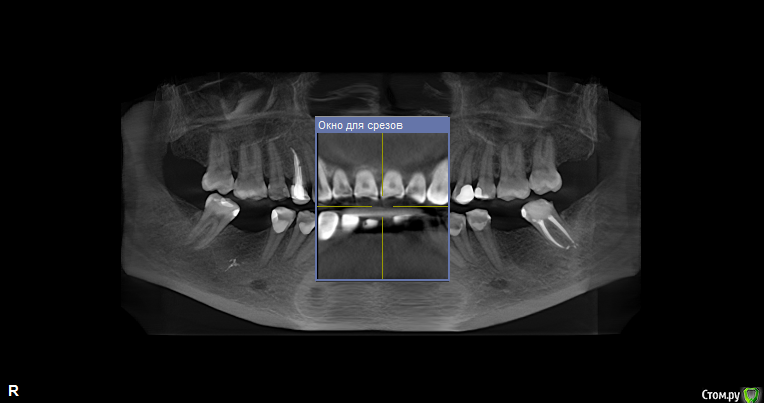

svetanik8 Опубликовано 25 мая, 2017 Поделиться Опубликовано 25 мая, 2017 Уважаемые врачи, прошу совета, чтобы определиться с тем, что делать.Году на 28м узнала, что у меня неправильный прикус (прямой), с детства отсутствует нижний передний зуб (детская травма, на тот момент врачи сказали, что зубы сойдутся, все будет ок, не сошлись, но мало кто видит, что его нет, улыбка как бы не такая низкая, чтобы открывать нижний ряд зубов).Лет в 25 удалили первую 6ку в нижнем ряду, спустя пару лет вторую симметрично, итого имею три проблемы, которые нужно решить (имплантация либо мост). Посетила пару врачей, один ортодонт предложил установить брекеты только на несколько нижних зубов с тем, чтобы сделать место для импланта на месте отсутствующего переднего, так как прикус меня 30 лет до этого не беспокоил, мне зубы кажутся ровными. Врач имплантолог в этой же клинике предложил по всем трем отсутствующим зубам сделать какое-то расщепление с подсадкой, при котором сразу же ставится имплант, причем обе шестерки предложил объединить в одну операцию, чтобы сэкономить на какой-то мембране.Второй врач сказал делать подсадку ткани по всем трем, по брекетам ничего не прокомментировал, отдельно нужно общаться с ортодонтом.И еще один врач тоже сказал, что нужно делать подсадку костной ткани, что расщепление ему не очень нравится в принципе, что может отломаться кость и тп. Подсадка костной ткани очень недешевая процедура (или я ходила в такие клиники дорогие, не знаю). Вопрос, стоит ли в моем случае делать импланты (по каждому зубу) или где-то лучше мост (например, семерка слева под коронку уже, там ползуба нет).Прилагаю снимки ОПТГ и КТ (скриншоты, если нужны другие ракурсы скажите, пока не разобралась как их делать).Отдельный вопрос по брекетам, не знаю выносить ли в отдельнуютему, проблема комплексная. На всякий случай еще фото обычные зубов.Спасибо заранее. Ссылка на комментарий

колесников Опубликовано 26 мая, 2017 Поделиться Опубликовано 26 мая, 2017 тактика зависит от предпочтений и умений доктора. все вышеизложенные методы могут быть применимы в вашем случае. с костной пластикой или без-это детали.Я бы не проводил костных пластик ,но это мое видение.Вобласти 31 необходима предварительная ортодонитеская подготовка Ссылка на комментарий